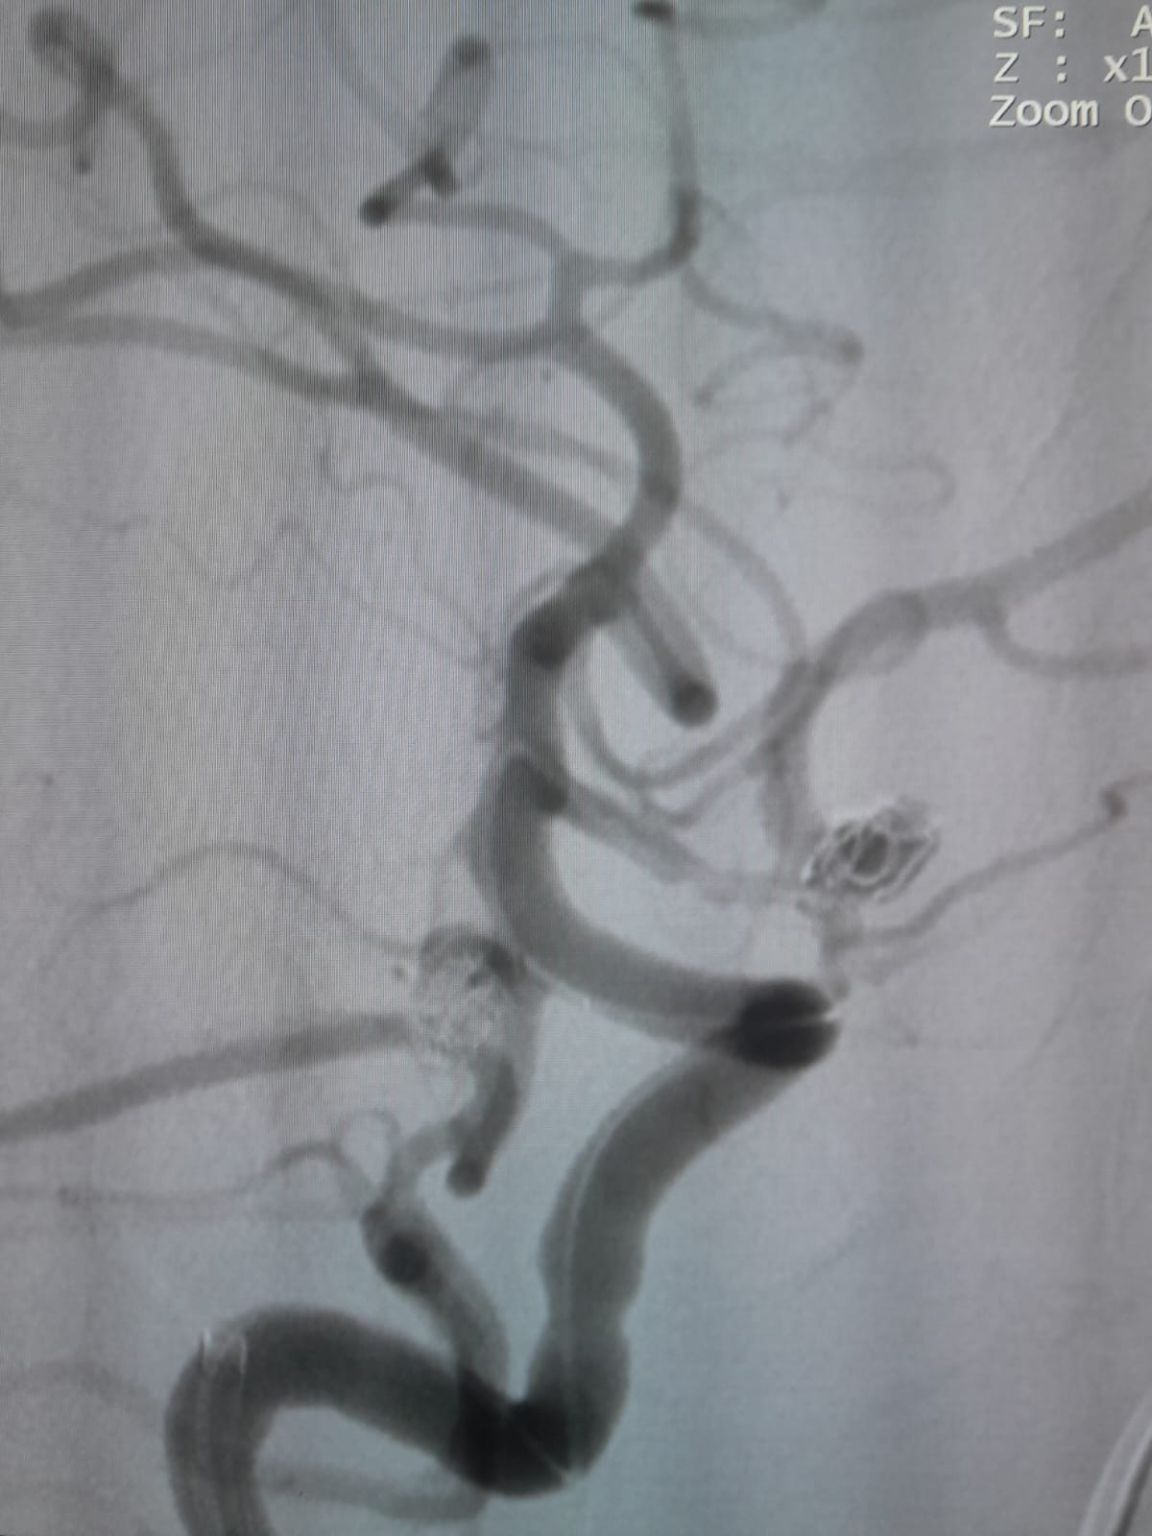

The patient was diagnosed with a newly discovered anterior communicating artery (AComA) saccular aneurysm and a posterior communicating artery (PComA) aneurysm that had been previously treated with coil embolization. Follow-up imaging revealed residual filling in the PComA aneurysm, requiring additional intervention.

The vascular access was established and the team then successfully navigated the Frepass® Disposable Microcatheter (TJMC14) to the target site. Embolization was performed using three Perdenser® Embolic Coil System (TJCST4.508-3D, TJCST0306-3D, TJCST0206-3D) deployed with the Deromper® Coil Detachment Controller (TJCDC).

During follow-up, residual filling was noted in the previously treated posterior communicating artery aneurysm. The team re-accessed the site using Frepass® Disposable Microcatheter (TJMC18 Plus) and successfully deployed a Nuva® Flow Diverter (TJED-D-4.5-16), which demonstrated ideal wall apposition and excellent flow diversion, leading to highly satisfactory treatment outcomes.